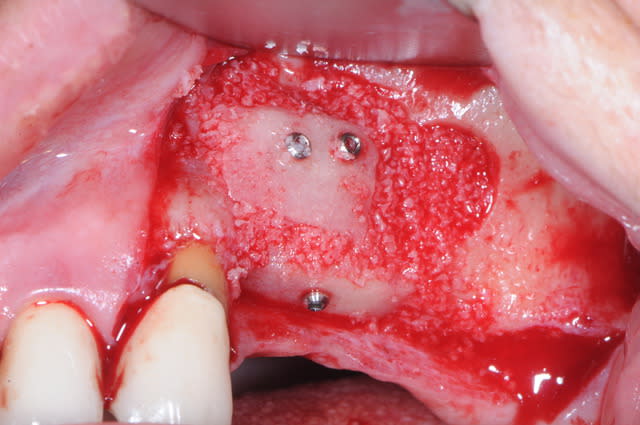

les vis STOMA de 1mm de diamètre j'adore !

et le biobank c'est quand même génial ce truc, on gagne un temps fou.

ici, avec le sinus lift réalisé avec le DASK (merci Michael B.) et avec la greffe d'apposition j' mis 1h45mm. un vrai bonheur !

Uniquement l'os Biobank en poudre, il a un aspect assez mou et agréable à manipuler.